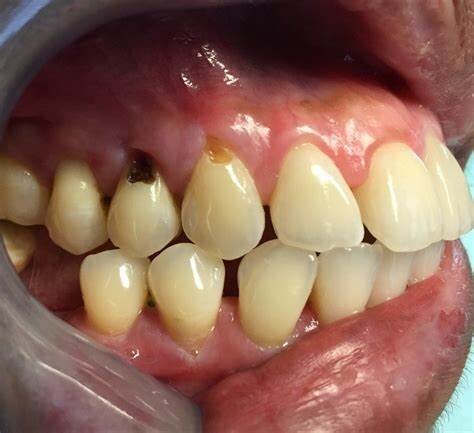

Causes of Gumline Cavities

A dental cavity forms when plaque, a sticky bacterial film that builds up inside the mouth, solidifies and creates an area of decay. This bacteria combines with sugar to produce acids that dissolve the tooth's enamel, the hard surface that works as a protective layer against tooth decay. And when this protective layer begins to wear, different types of cavities have the potential to form.

Have you ever wondered what areas of the mouth are most prone to tooth decay? Well, not all teeth are created equal. Plaque tends to accumulate more easily in certain areas. For example, the back teeth' pits and fissures (molars) are a hot spot for plaque and the spaces in between the teeth. Plaque also builds up easily along the gumline, and when this plaque isn't removed, a gumline cavity can form.

Gumline cavities can also be associated with exposed tooth roots. Gum tissue usually protects the roots, but the roots will be vulnerable if the gum tissue recedes. That's because roots are covered in a material called cementum, which is much weaker than tooth enamel.